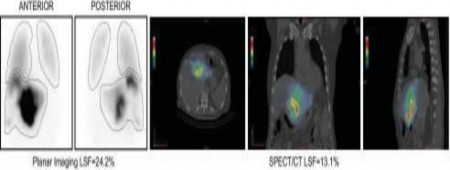

Thông thường, shunt gan – phổi được tính toán bằng cách sử dụng công thức tính toán giữa hoạt độ phóng xạ ở phổi với hoạt độ phóng xạ ở gan và phổi[8]. Hoạt độ phóng xạ này được xác định bằng kĩ thuật SPECT với 99mTc

– MAA mô tả độ tập trung của các hạt 99mTc – MAA ở nhu mô gan và phổi. Nhược điểm của kĩ thuật này là không xác định được chính xác thể tích quan tâm và ước tính thấp các thông số cần thiết [31].Hơn nữa, sự hấp thu 99mTc – MAA trong vòm gan có thể đưa số lượng phóng xạ vào đáy phổi và gây sai lệch trong quá trình tính toán[56]. Một phương pháp khác đánh giá hình ảnh shunt gan – phổi là SPECT / CT, nó ưu điểm hơn SPECT ở chỗ cung cấp thông tin về thể tích với hình ảnh 3D cho phép xác định chính xác cấu trúc giải phẫu gan, phổi và các các cấu trúc khác. Hiện nay, 99mTc – MAA SPECT/CT được khuyến cáo sử dụng để mô phỏng phân bố hạt vi cầu gắn 90Y. 99mTc – MAA SPECT/CT sau điều trị cần được đối chiếu với SPECT thông thường[18]. Một vài nghiên cứu cho thấy 99mTc – MAA SPECT/CT tương quan tốt với SPECT trong đánh giá chỉ số giữa khối u và gan lành có giá trị phát hiện các vị trí bắt xạ ngoài gan để phân tầng tổn thương các cơ quan lành do xạ trị[23] Nghiên cứu của tác giả Mai Hồng Sơn, Nguyễn Bình An và Lê Ngọc Hà trên 52 bệnh nhân ung thư gan nguyên phát được điều trị xạ trị chiếu trong chọn lọc tại bệnh viện 108 cho thấy 99mTc – MAA SPECT/CT tương đồng với SPECT , xác định chính xác thể tích u điều trị (loại bỏ vùng hoại tử)[18].

Hình 1.4: Hình ảnh shunt gan – phổi hai kĩ thuật SPECT và SPECT/CT (Nguồn Mike F.Goergiou, Russ A.Kuker, Matthew T.Studenski, 2021[22])